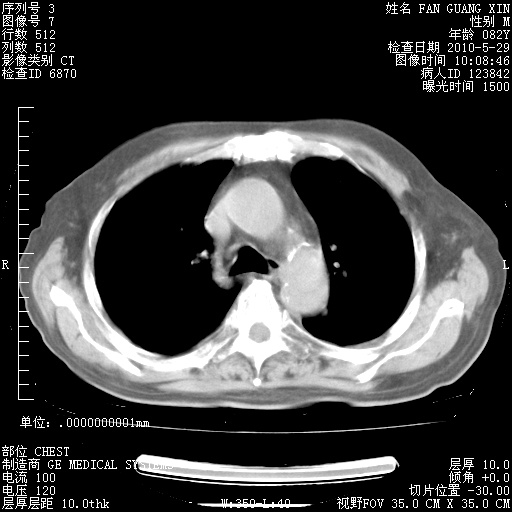

再治疗10天后的肺部CT

再治疗10天后的肺部CT 纵膈窗

肺部体征:呼吸25次/分,心率100次/分,呼吸音增粗。无干湿罗音。

血常规:15.36×10 [sup]9[/sup]/L  N0.92  L0.036  M0.045 ESR 27mm/h。

血生化:白蛋白33.30g/L  球蛋白23.67g/L  CRP 32.82mg/L 肝肾功能正常。电解质正常。

从白细胞总数和中性比例看好像合并感染。肺部纹理好像比上次多,支气管炎?其他感染?

阅读此次胸部CT,肺间质渗出性改变较入院时有吸收。目前从体温、白细胞、中性分叶明显增高,肯定存在细菌感染(发生医院感染哦,若无消化道及泌尿系统等感染的依据,肺部感染可能大)。若你院头孢哌酮舒巴坦钠耐药率较高,同意你的方案,若48小时体温仍高,可考虑使用碳青霉稀类抗菌药物,同时可予超声雾化、注意滴数时加大液体量。白蛋白33.30g/L较低哦,需加强营养等支持治疗。